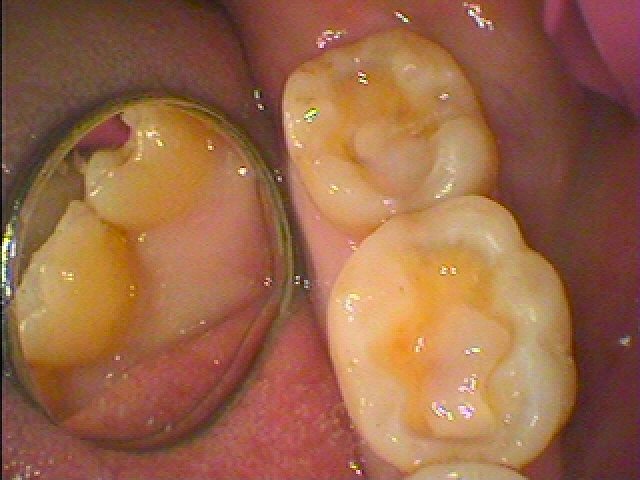

セレックセラミックにて修復しています

右下の奥歯の銀歯を外していきます